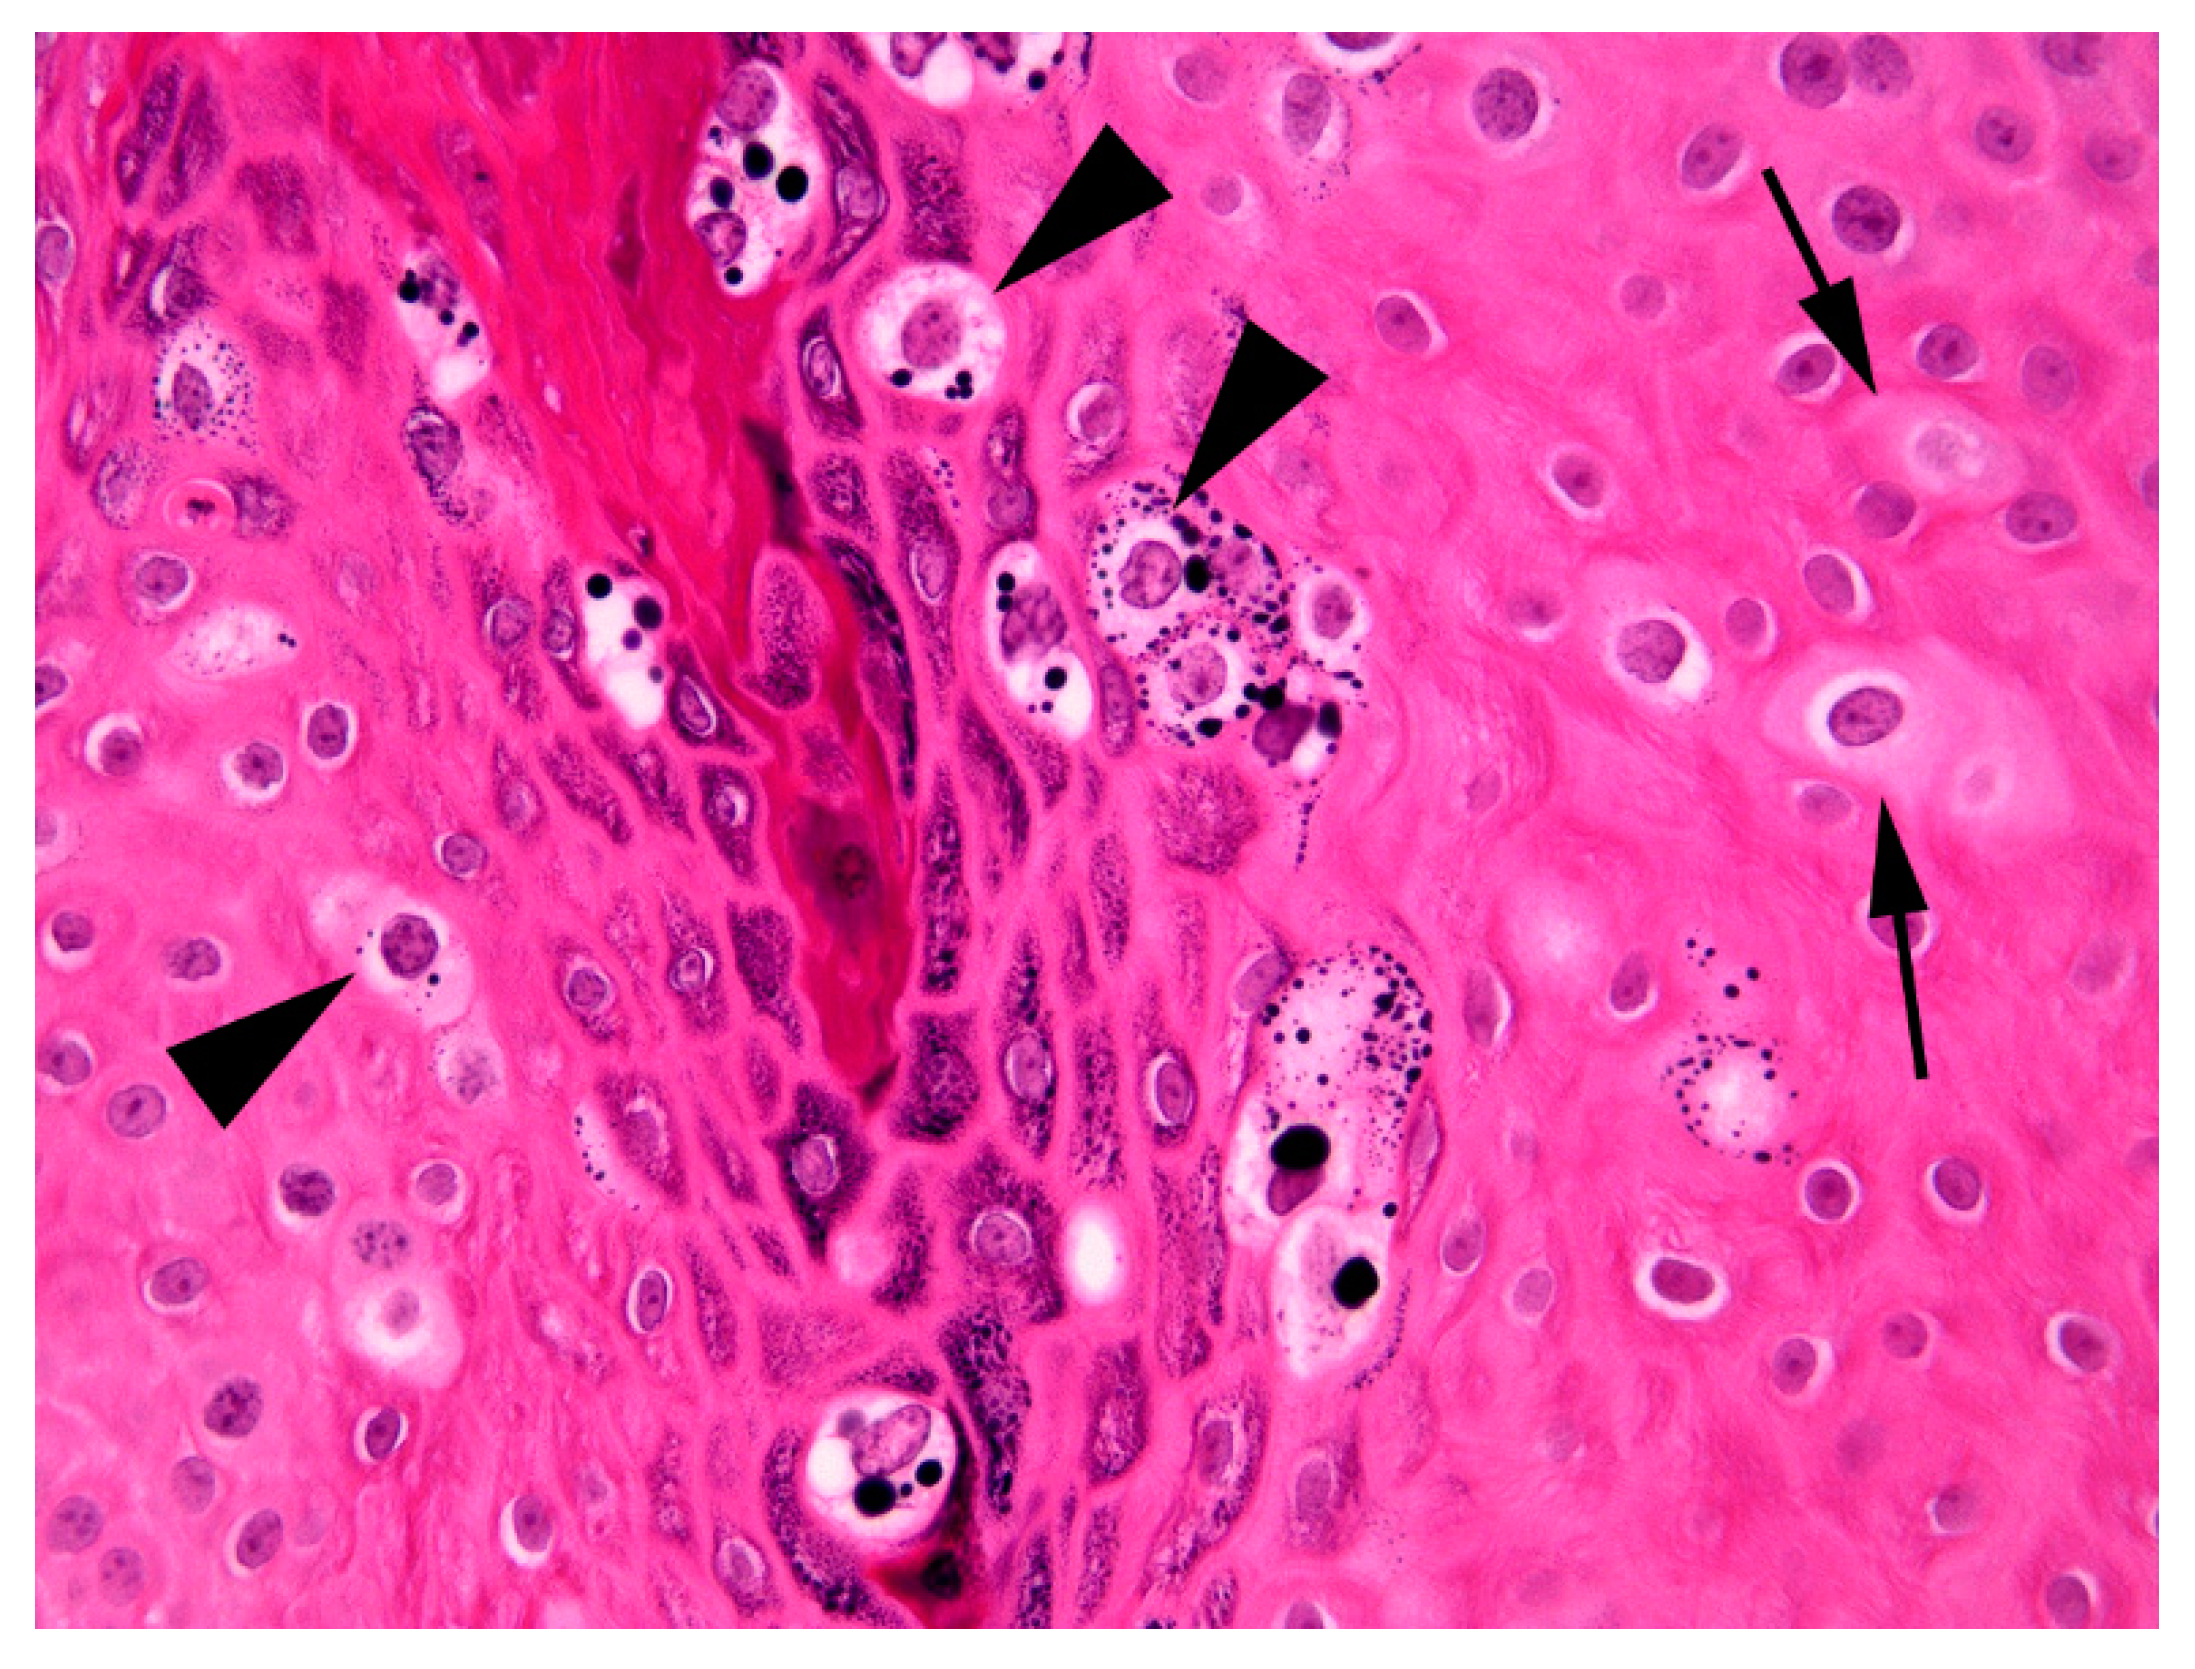

The thickening was well-demarcated and surrounding epidermis appeared within normal limits. Examination of the thickened epidermis revealed that orderly maturation was maintained and the proliferative lesion was covered by marked dense orthokeratosis. There was no evidence of invasion of the basement membrane and few inflammatory cells were visible within the superficial dermis or within the deeper layers of the hyperplastic epidermis. Scattered within the superficial aspects of the stratum spinosum and the stratus granulosum were numerous keratinocytes that were enlarged by increased quantities of pale blue cytoplasm (Figure 3).

Cells within the superficial epidermis that showed this change also often contained large numbers of clumped keratohyalin granules. In addition to the large cells with blue-grey cytoplasm there were also smaller numbers of cells that had a shrunken nucleus surrounded by a clear halo (koilocytes). The enlarged cells with blue-grey cytoplasm and koilocytosis were considered consistent with PV-induced cell changes and a diagnosis of a viral squamous papilloma (wart) was made.

As infection by PVs is often asymptomatic [17], simply detecting a PV within a lesion does not prove causality. However, many of the histological features in the present case are considered to be characteristic of PV-induced papillomas in horses as well as in other species [18]. These features include the presence of folded epidermis due to an area of well-demarcated epidermal hyperplasia. This change occurs as the PV infection stimulates expansion of the epidermis. Importantly, as observed in the present case, the PV does not alter the normal maturation of the epidermis as would be seen in pre-neoplastic or neoplastic epidermal lesions. Additionally, PV-induced cytopathic changes were visible in the hyperplastic epidermis. These changes included the presence of enlarged cells with blue-grey cytoplasm, clumping of keratohyalin granules, and koilocytosis [18].

Figure 3. Photomicrograph of the mass from the fetlock. Enlarged cells that have increased quantities of blue-grey cytoplasm are visible within the thickened epidermis (arrows). Additionally, enlarged cells that have shrunken nuclei that are surrounded by a clear cytoplasmic halo (koilocytes; arrowheads) are also visible. Note also the prominent clumping of keratohyalin granules superficially within the lesion. H&E 400×.